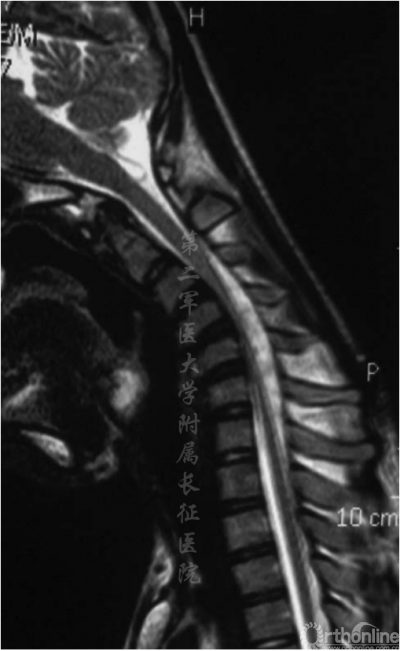

图2.术前屈曲位MRI显示颈硬膜囊向前移位和颈脊髓受压变平

颈椎中立位MRI可见颈椎后凸在C4-C5或C5-C6处具有顶点(图1),且脊髓出现轻度萎缩。屈颈位MRI可见硬膜外高信号影及硬膜囊后壁前移(图2)。头颅MRI未显示异常。根据MRI将患者诊断为平山病伴颈椎后凸畸形。入院三天后,患者在全麻下接受颈前路椎间盘切除术并在C3-C7水平融合以重建颈椎序列和脊柱前凸(图3)。